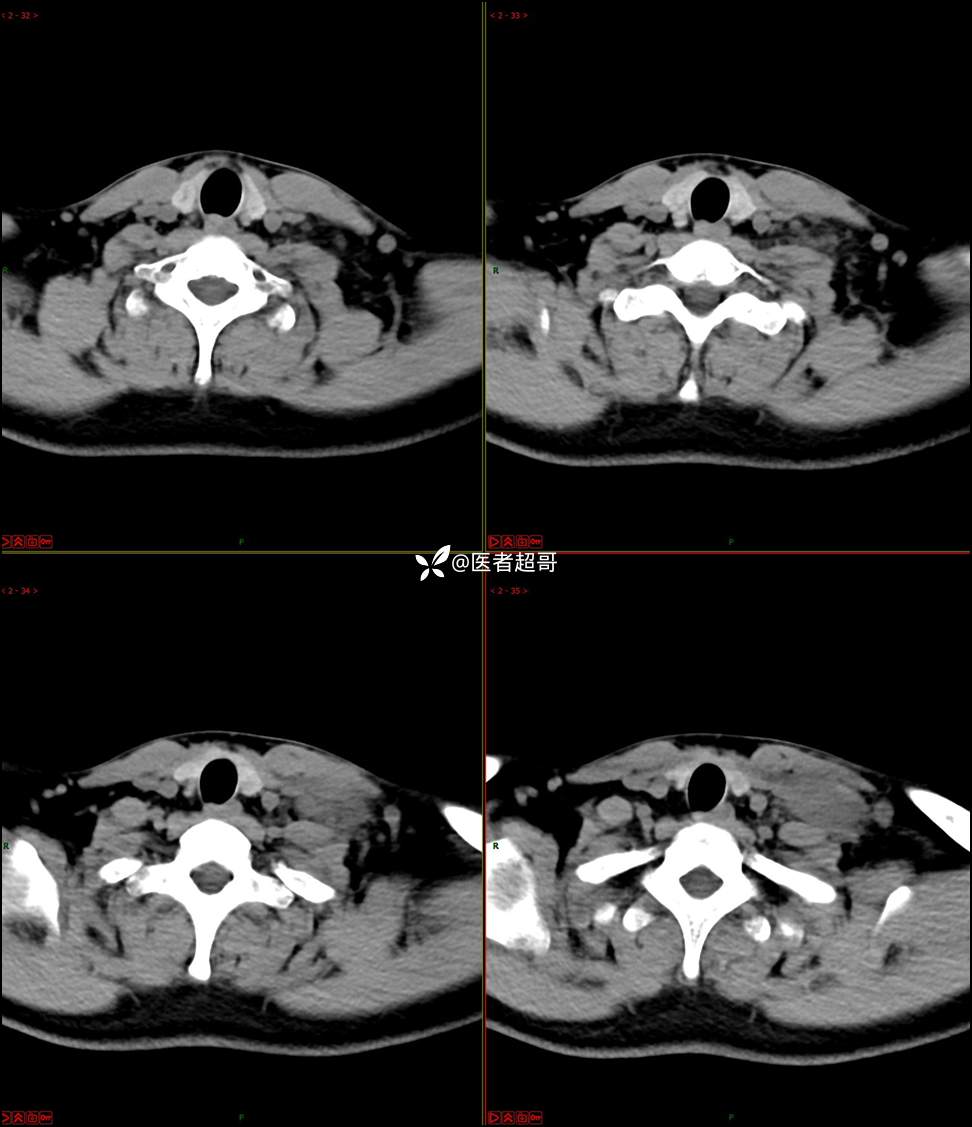

现病史:患者自述10余天前无意中发现左侧颈部一肿物,颈部活动时、进食时伴疼痛,无发热,患者前往人民医院就诊,给予输液治疗(头孢呋辛钠2g bid 硫酸阿米卡星0.4g qd、)10天,患者感肿物轻微变小,后患者为求进一步治疗,昨日来我院门诊就诊,给予颈部彩超示:左颈部实性肿物,神经来源?,左颈部肿大淋巴结;颈部ct平扫+强化示:左侧锁骨上区占位,神经鞘瘤?双侧颈部多发淋巴结;门诊以“局部肿物”收治入院,患者自患病以来,神志清,精神可,饮食睡眠可,体重无明显变化,二便正常。